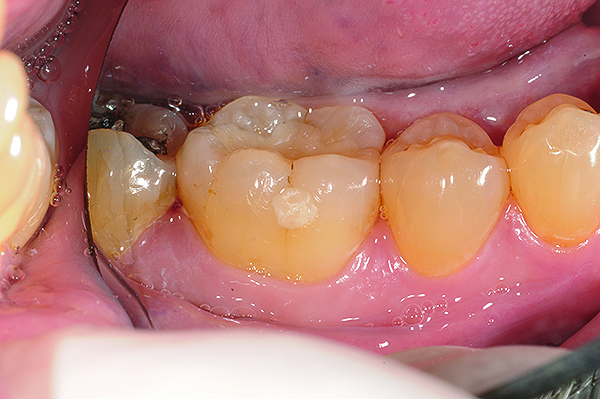

The case demonstrated in Figure 6 through Figure 11 shows the ease with which non-carious Class V lesions can be handled with bulk-filled GIC restorations. Several cervical lesions (abfractions) of significant depth in permanent posterior teeth showed signs of turning carious (Figure 6). The author elected to restore them with the EQUIA technique. For non-carious lesions it is only necessary to freshen the cavity surface and margins with a diamond or carbide bur and to remove any visibly damaged hard tissue. It is then most ideal to remove any smear layer by treating the cavities with a weak acidic solution such as 20% polyacrylic acid (Figure 7). It is important that the clinician not substitute this acidic solution with a conventional phosphoric acid solution or gel used for etching tooth structure prior to resin bonding, as using the conventional solution will remove important mineral content that the GIC requires to bond with chemically. Once the cavities were isolated, a high-viscosity auto-curing GIC was mixed and syringed into the cleaned cavities with a bulk-fill technique (Figure 8). A plastic instrument was then used to condense and shape the material to the cavity walls and margins. The GIC will set in approximately 2:30 seconds to a sufficient level where it is safe to begin adjusting and finishing with rotary instruments. After the restorations were finished, they were coated with a nanofilled, light-cured resin glaze (Figure 9 and Figure 10). The glaze protects the surface of the GIC while it sets completely and enhances the physical strength of the final restoration. The completed GIC restorations (Figure 11) showed excellent esthetics comparable to composite resin.

Fig 9 and Fig 10. After GIC was manually condensed and shaped, a nanofilled resin glaze was liberally applied to the surface of the finished restoration (Fig 9) and light-cured (Fig 10).